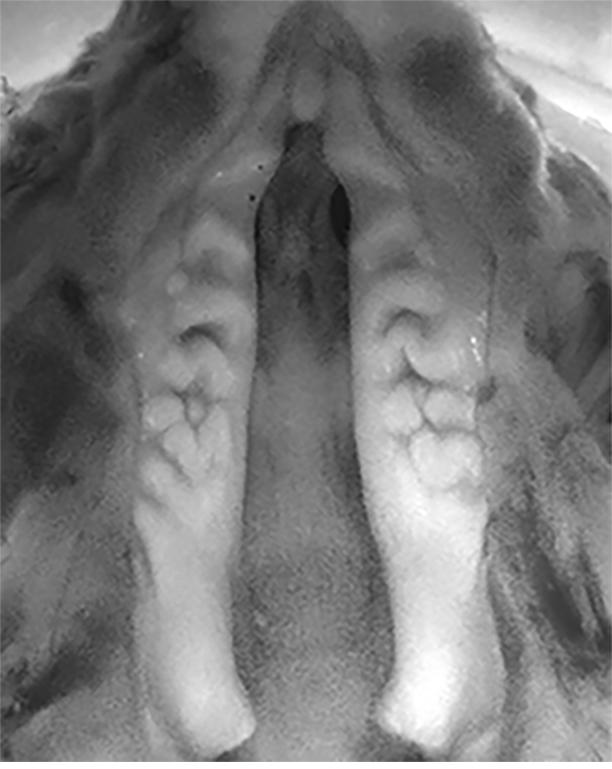

From www.researchgate.net

Definitive casts obtained from different palatal vault rounded (V A When Does The Palate Form In Utero How does the palate form? The face starts to develop around week four until week 6 of prenatal life. The palate undergoes complex morphological changes during embryogenesis to. Development begins during week 5, but fusion of its component parts is not complete until week 12. The primary palate is otherwise known as the intermaxillary segment and the protrusions. The palate. When Does The Palate Form In Utero.